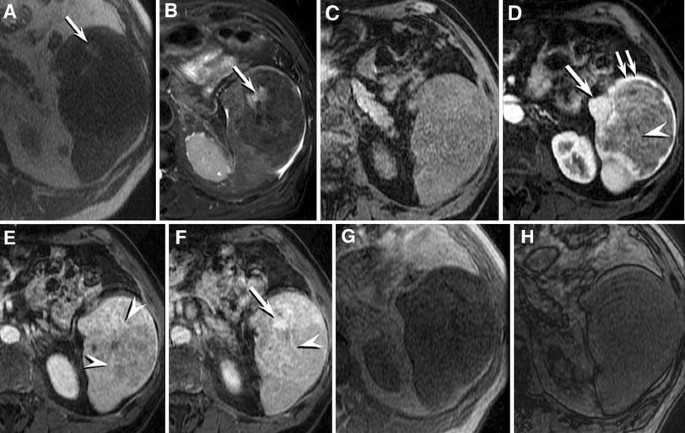

Fig. 3

figure 3

SANT of the spleen: MR findings. Axial T1-weighted [TR = 690 ms, TE = 40 ms] (A) and T2-weighted fat saturation [TR = 16000 ms, TE = 91 ms] (B) images show the lesion to be predominantly low signal on both sequences, with a few foci of relatively hyperintense T1- and T2-weighted signal (arrows) representing foci of hemorrhage. Unenhanced (C) and arterial (D), venous (E) and delayed (F) enhanced axial 3D T1-weighted gradient echo images with fat saturation [LAVA, TR = 4.5 ms, TE = 2.2 ms] images show initial intense enhancement of the periphery of the lesion (double arrow) with progressive appearance of thin enhancing septae (arrowheads) penetrating the center of the lesion from the periphery. Areas of nodular enhancement (arrows) correlate with the presence of angiomatoid nodules (compare with gross pathological appearance in Fig. 5). Axial in-phase [TR = 180 ms, TE = 2.4 ms] (G) and out-of-phase [TR = 180 ms, TE = 2.4 ms] (H) images show a progressive signal increase on the shorter TE sequence (H), consistent with the presence of iron within the lesion. Pathological analysis shows that iron within SANT of the spleen is likely due to the presence of blood products.

The presence of signal changes on MR imaging suggesting the presence of iron initially supported the impression of extramedullary hematopoiesis as the etiology of the splenic lesion in this patient. However, iron deposition may occur in a number of conditions unrelated to extramedullary hematopoiesis, and it is likely that the hemorrhagic nature of splenic SANT accounts for this MR imaging appearance.